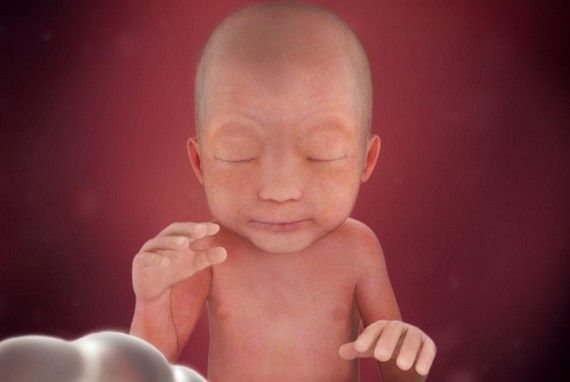

يستمر رأس الجنين في النمو حتى يصل إلى نصف حجم جسمه تقريباً ويبدأ الجسد بالنمو وتتكون خلايا الدم الحمراء في الكبد، يحدث إغلاق لجفون الجنين وتستمر هكذا حتى الأسبوع الثامن والعشرين ولكن يبدأ وجه الجنين بالتشكل والتحدد بشكل اوضح وتطول الأطراف وتصبح أنحف.

خلال نهاية هذا الأسبوع تبدأ الملامح الخارجية للجهاز التناسلي بالظهور والتشكل ويصبح وزن الجنين حوالي 8 جم.